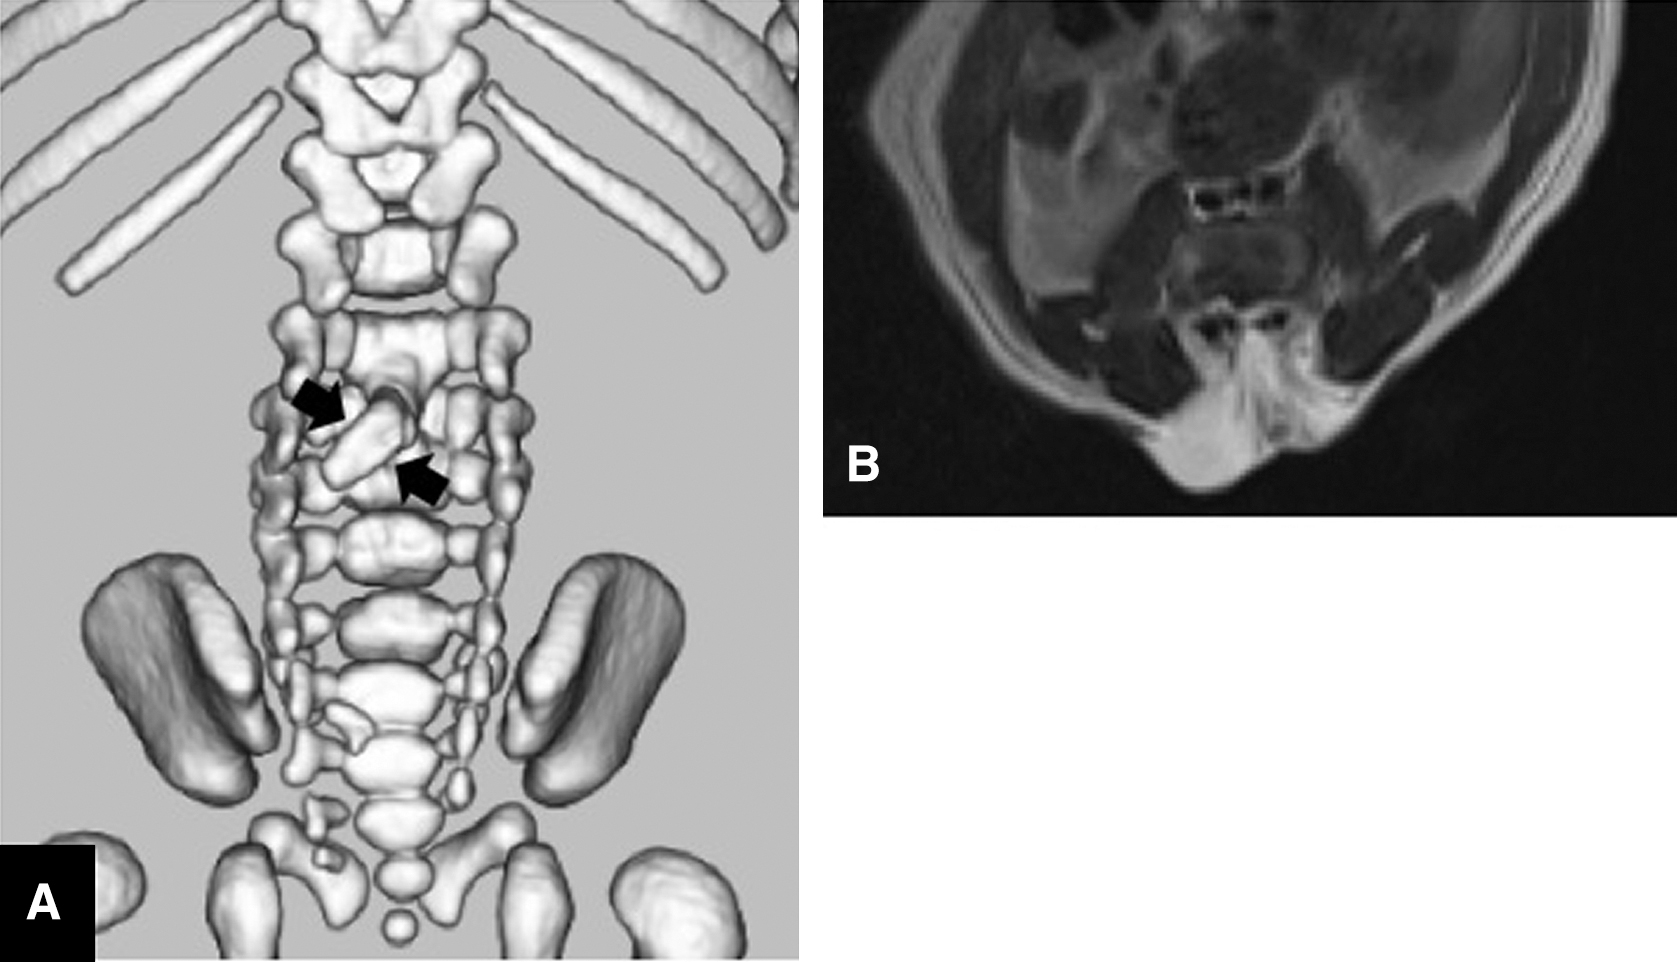

A male infant was diagnosed with hydrocephalus at 26 weeks of gestation based on an intrauterine ultrasound examination. Magnetic resonance imaging (MRI) conducted at 30 weeks of gestation revealed a lumbosacral lesion. The infant was delivered by cesarean section at 38 weeks of gestation. We observed a bulging sac and skin defect in the center of the lumbar region (Fig. 1), but no atrophic changes or clubfoot deformities were seen. A neurological examination revealed slight spasticity of the legs without any apparent paralysis. Three-dimensional computed tomography (3D-CT) revealed spina bifida of the lumbosacral region and bony septum formation just posterior to the L3 vertebral body (Fig. 2A). MRI showed a split cord on T2-weighted axial images (Fig. 2B). The preoperative diagnosis was an open MMC associated with a type I SCM.